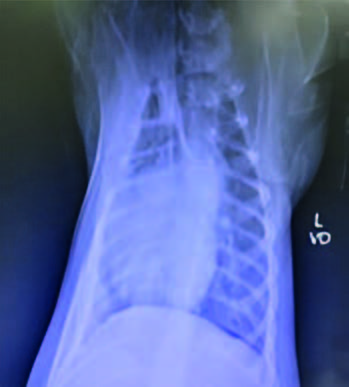

This case study involves a 5-monthsold, intact male Golden Retriever dog presented with tetraparesis, seizure and comatose by a car accident 5 days ago. Physical examination presented unconsciousness, tetraparesis, tachypnea, right temporomandibular joint (TMJ) luxated and crepitus of left humerus. Neurological examination was localized to cerebral cortex and brain stem lesions. The Modified Glasgow Coma Scale (MGCS) was 3. Laboratory tests revealed anemia of 23.1% (reference range, 35-45%), leukocytosis of 19.09 x 103/μL (reference range, 5-14.1 x 103/μL). Radiography was presented to skull fracture, lung hemorrhage (Figure 1) and left humerus fracture (Figure 2).